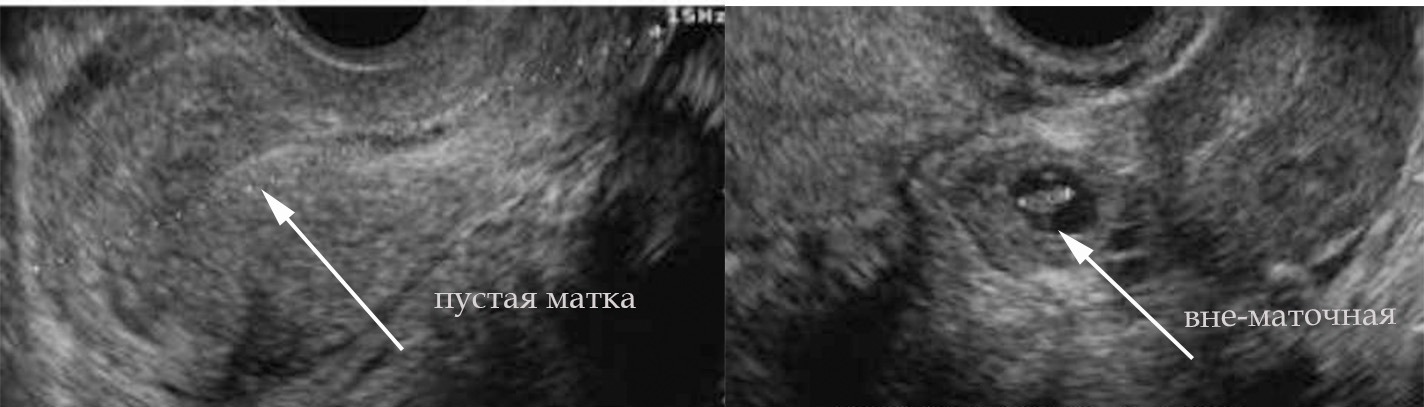

Для выполнения УЗИ на раннем сроке должны быть показания. Основная цель —установить маточную локализацию плодного яйца: маточная, внематочная; вторая цель — определить жизнеспособность плодного яйца. Анатомия и все остальное — уже ближе к первому скринингу в 11-14 недель, но УЗИ в ранние сроки в основном преследуют эти две цели. По определенным ультразвуковым параметрам их возможно сделать.